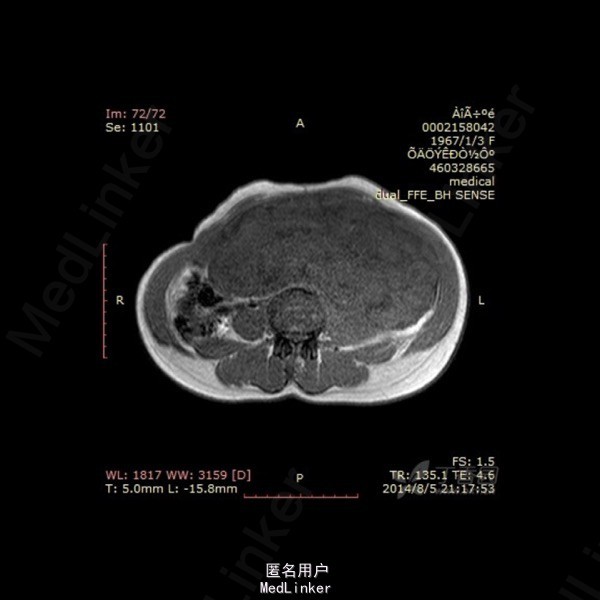

影像表现:左侧附件区示一巨大的病变,呈长T1长T2异常信号影,期内多发分隔,增强后呈不均匀强化,强化较明显。DWI示低信号。总的来看,病变为一个巨大肿块,内有分隔,境界较清。 诊断:我认为首选左侧阔韧带子宫肌瘤可能性大。由于其短期内增大,不除外瘤内出血的可能。 转于:丁香园